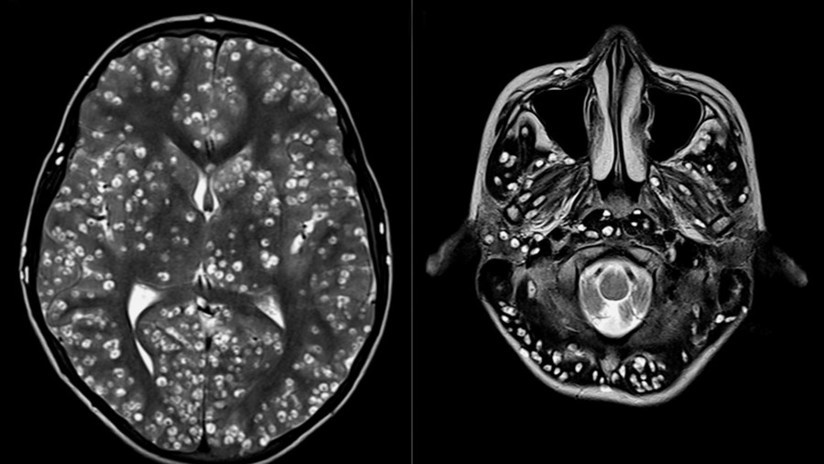

Tras practicarle una resonancia magnética y exámenes de ultrasonido, los especialistas encontraron que la corteza cerebral y el tronco encefálico del paciente estaban llenos de larvas.

El muchacho padecía neurocisticercosis, una enfermedad parasitaria originada cuando una persona ingiere huevos microscópicos de una tenia porcina y que afecta al tejido muscular. De ahí los parásitos se propagan al cerebro. Los personas infectadas pueden pasar mucho tiempo sin presentar síntomas.